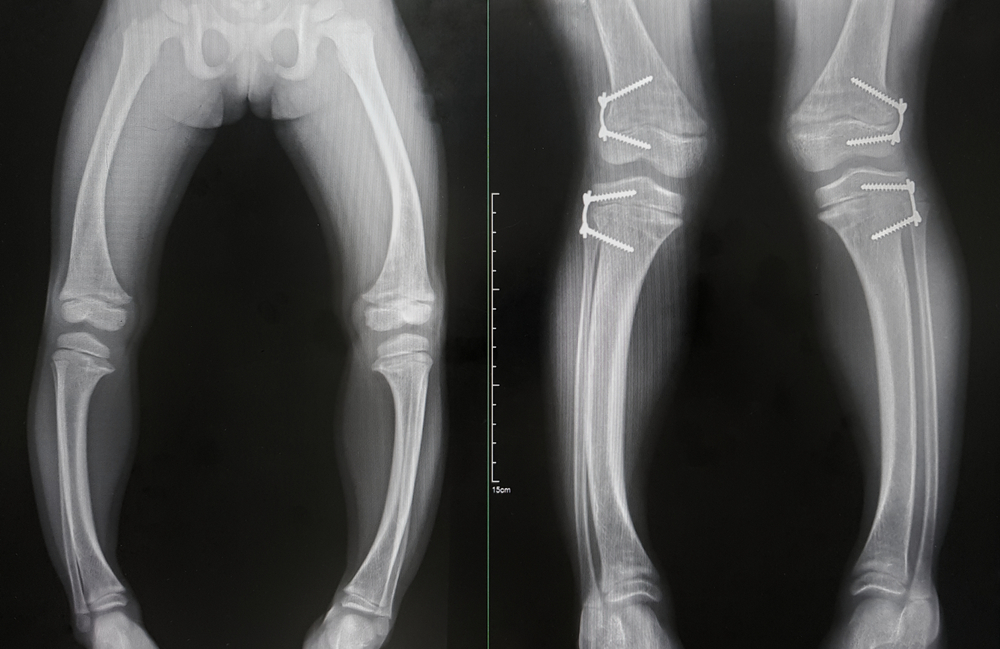

ជំងឺឆ្អឹងទន់ សំដៅទៅលើករណីទន់ឆ្អឹងបណ្ដាលមកពីកង្វះវីតាមីន D បង្កឲ្យបាក់ឆ្អឹងទាំងមនុស្សចាស់ ក្មេងៗ ខណៈមនុស្សពេញវ័យ អាចបណ្តាលឲ្យទៅជាកោងឆ្អឹង ពិសេសឆ្អឹងនៅត្រង់ជើងសម្រាប់ទប់លំនឹង និងទ្រដងខ្លួនជាដើម។

ជំងឺនេះខុសពីពុកឆ្អឹងត្រង់ថា ពុកឆ្អឹងធ្វើឲ្យឆ្អឹងស្ដើងជាងមុន និងងាយបាក់។ មនុស្សពេញវ័យគេហៅថារោគឆ្អឹងទន់ ចំពោះក្មេងគេហៅជំងឺ Ricket ភាគច្រើនកើតលើស្ត្រី និងពេលខ្លះស្ត្រីកំពុងមានផ្ទៃពោះ ក៏អាចកើតដូចគ្នា។